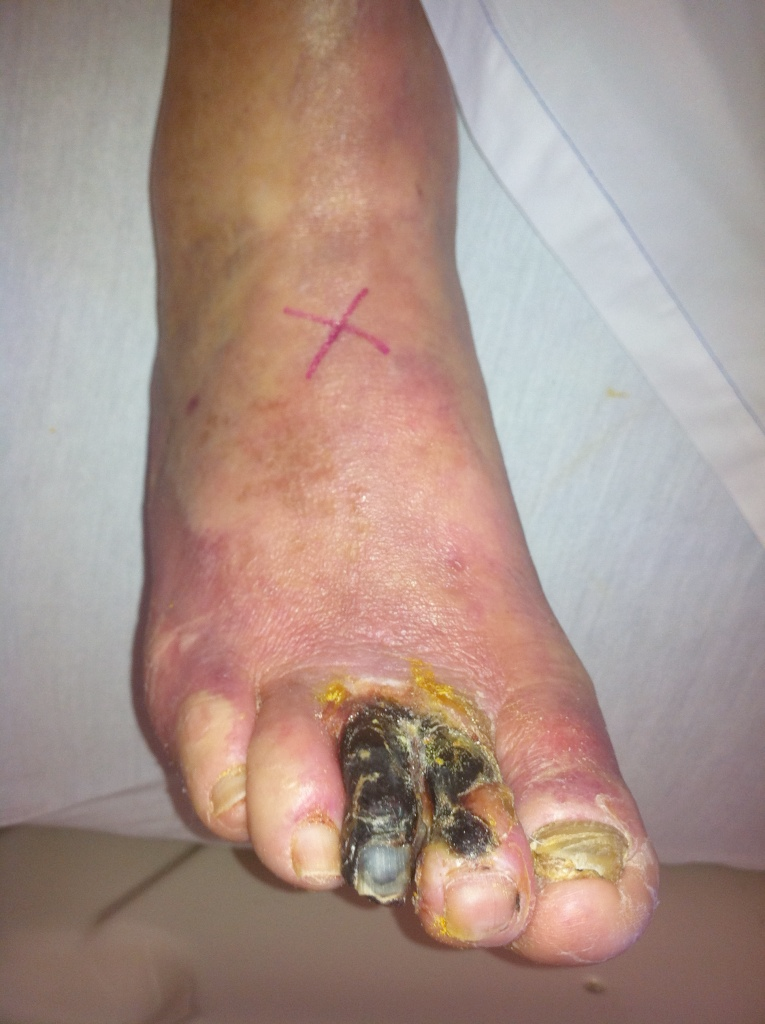

Once a nodule is deemed to be of concern, surgery is often advised. Surgical removal of the thyroid gland is known as thyroidectomy. If the nodule is clearly cancerous, the entire gland is removed in an operation called total thyroidectomy. This is a common operation, first performed by Professor Theodor Billroth in the 1860s in Europe. If the nodule has worrisome features based on the ultrasound scan or biopsy, some surgeons may choose to remove just half the gland first in an operation known as hemithyroidectomy or thyroid lobectomy. The nodule may then be sent for further analysis before the surgeon proceeds with further surgery.

The technique of thyroidectomy has evolved substantially. Technology has made this surgery safer and more effective. Amongst the more notable improvements is the use of nerve integrity monitoring which reduces the risk of nerve damage during which may affects the patient’s voice. The harmonic scalpel is another instrument which reduces blood loss from surgery and is associated with less pain following surgery.